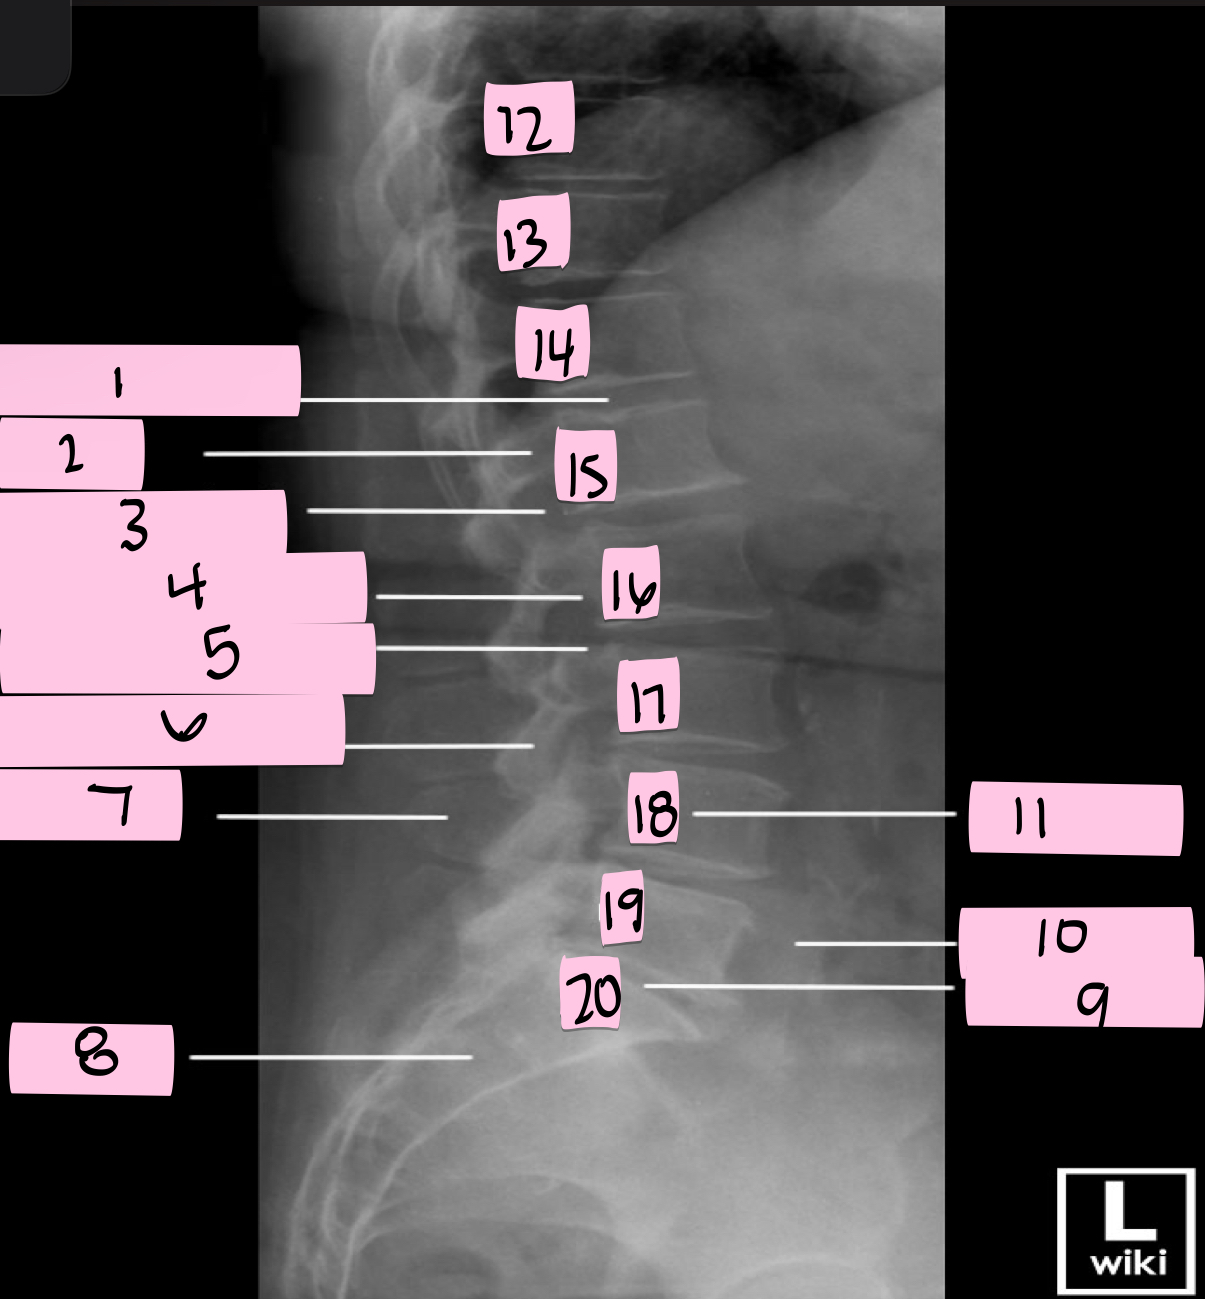

What is 1 pointing to?

Superior articular process

What is 2 pointing to?

Zygapophyseal joint

What is 3 pointing to?

Transverse process

What is 4 pointing to?

Pars interarticularis

What is 5 pointing to?

Inferior articular process

What is 6 pointing to?

Pedicle

What is 7 pointing to?

Scotty dog